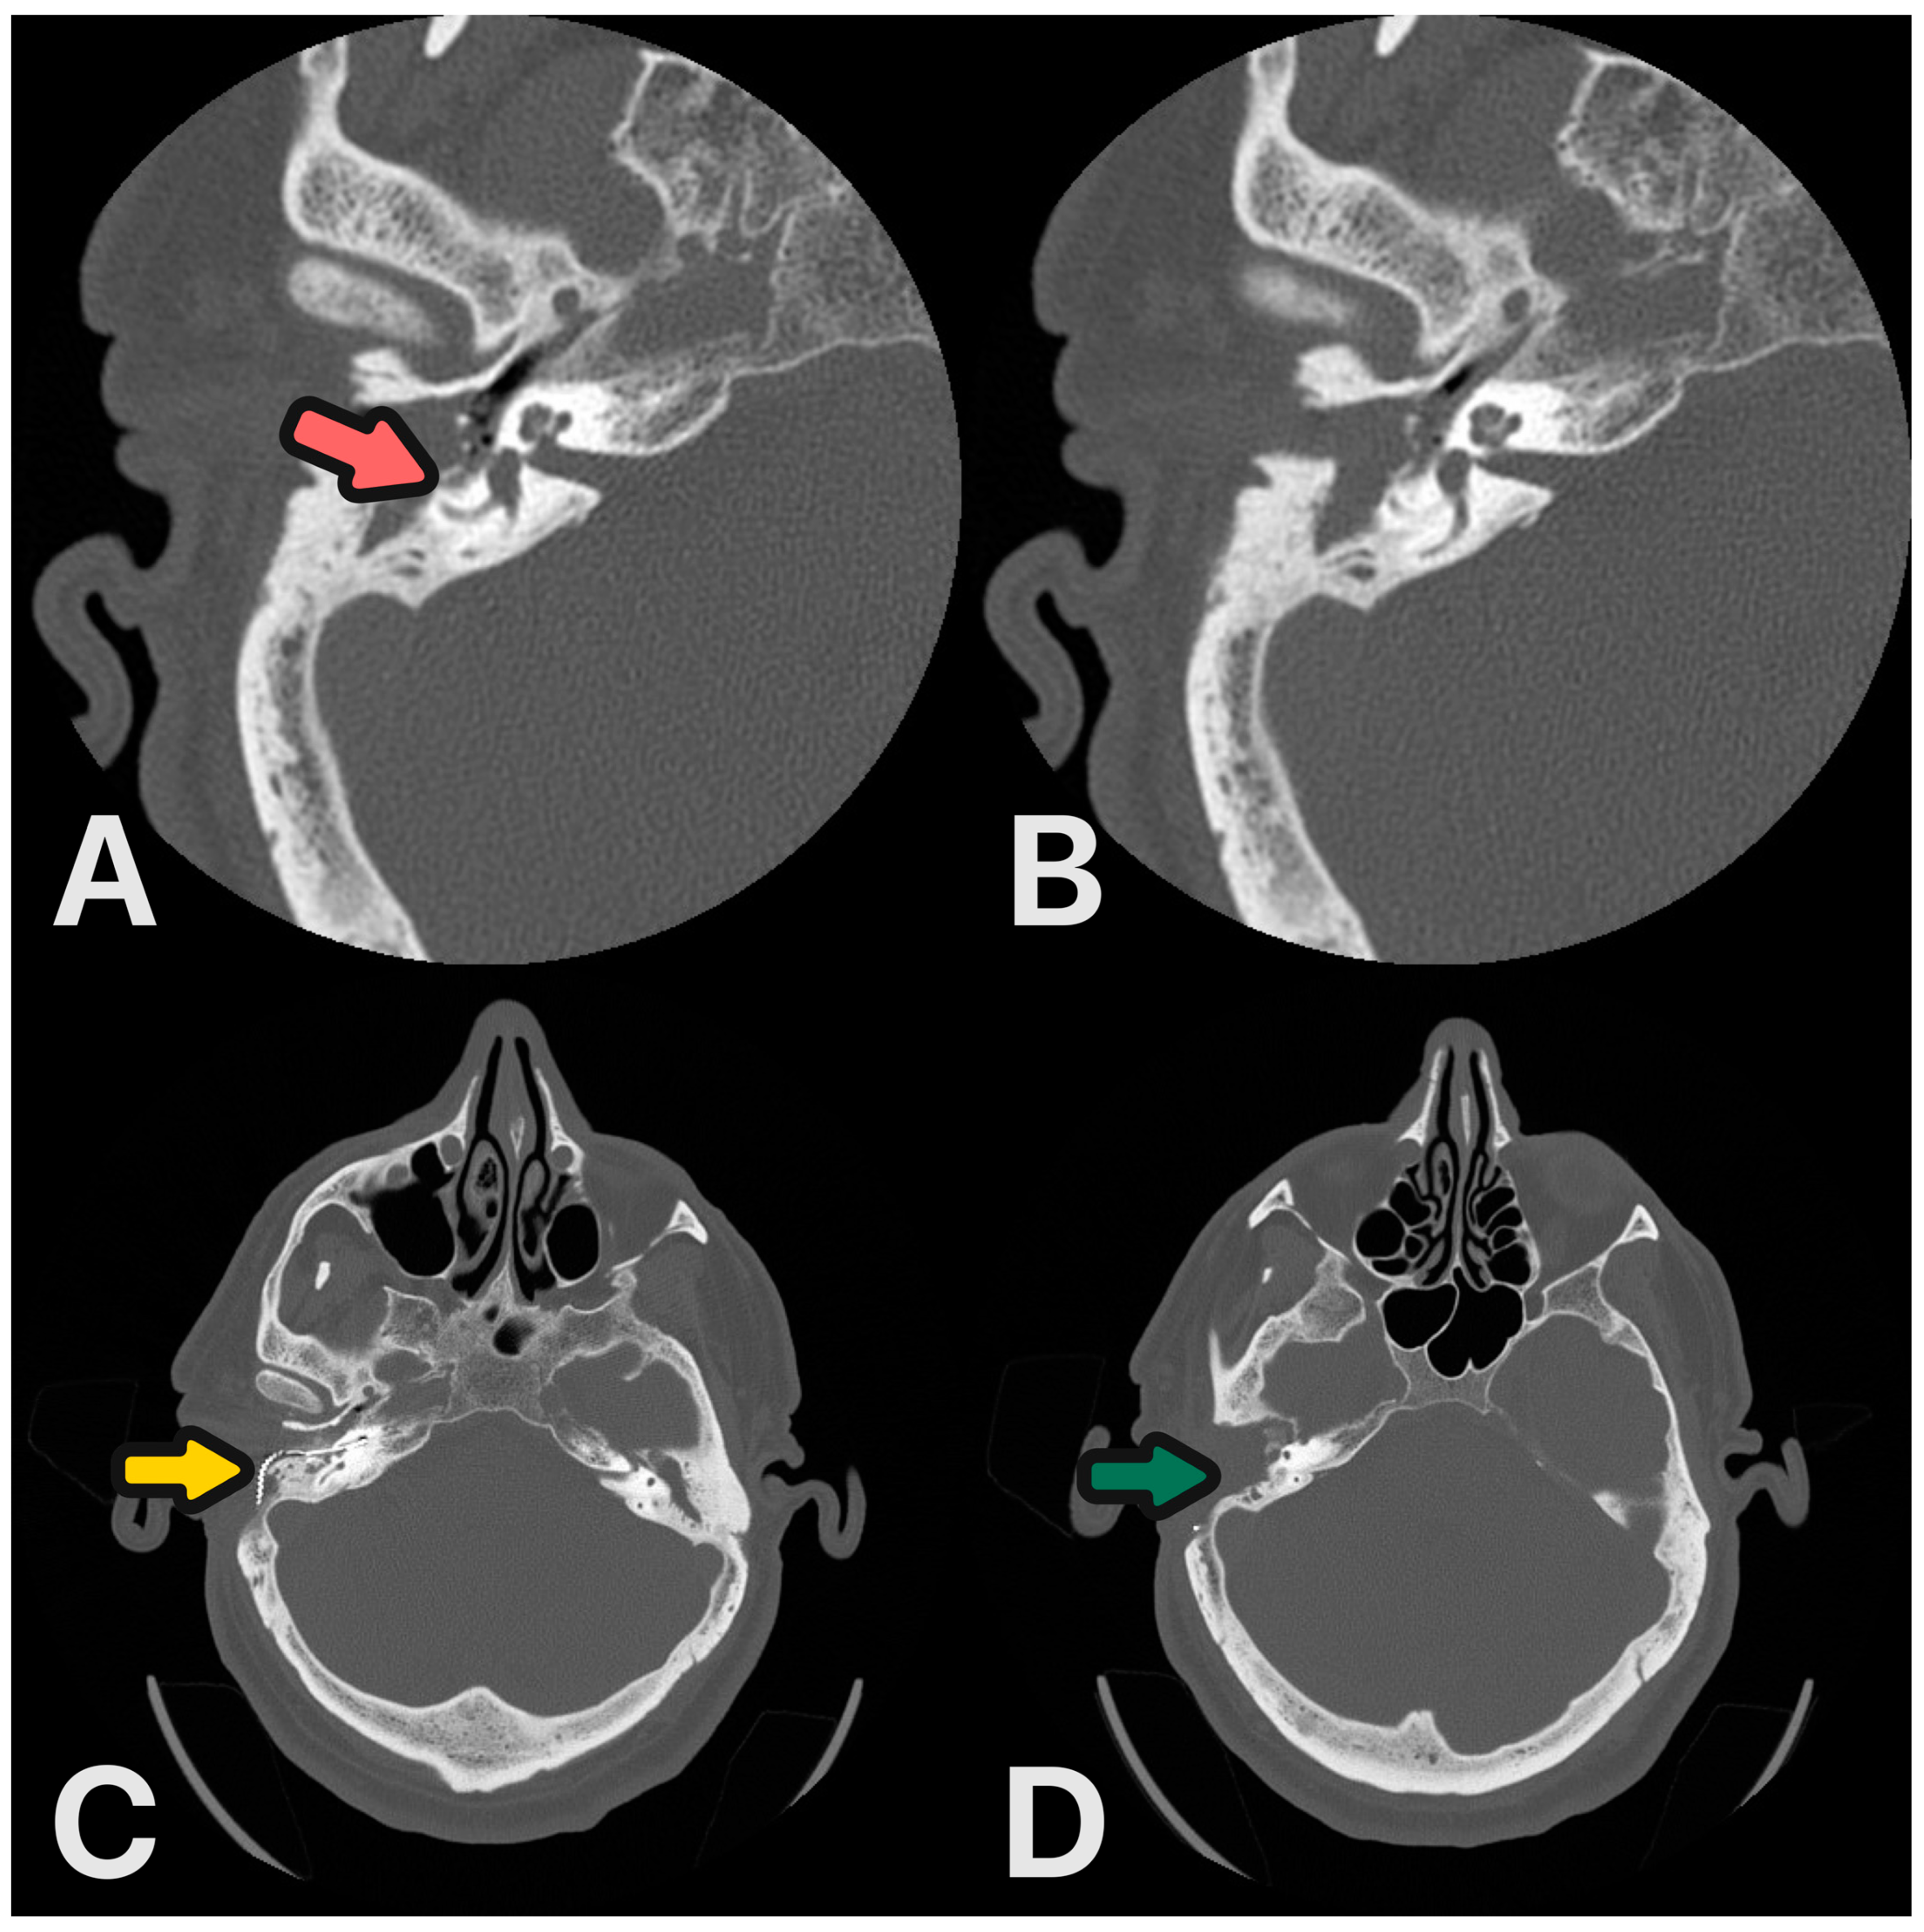

3.3. Case 3